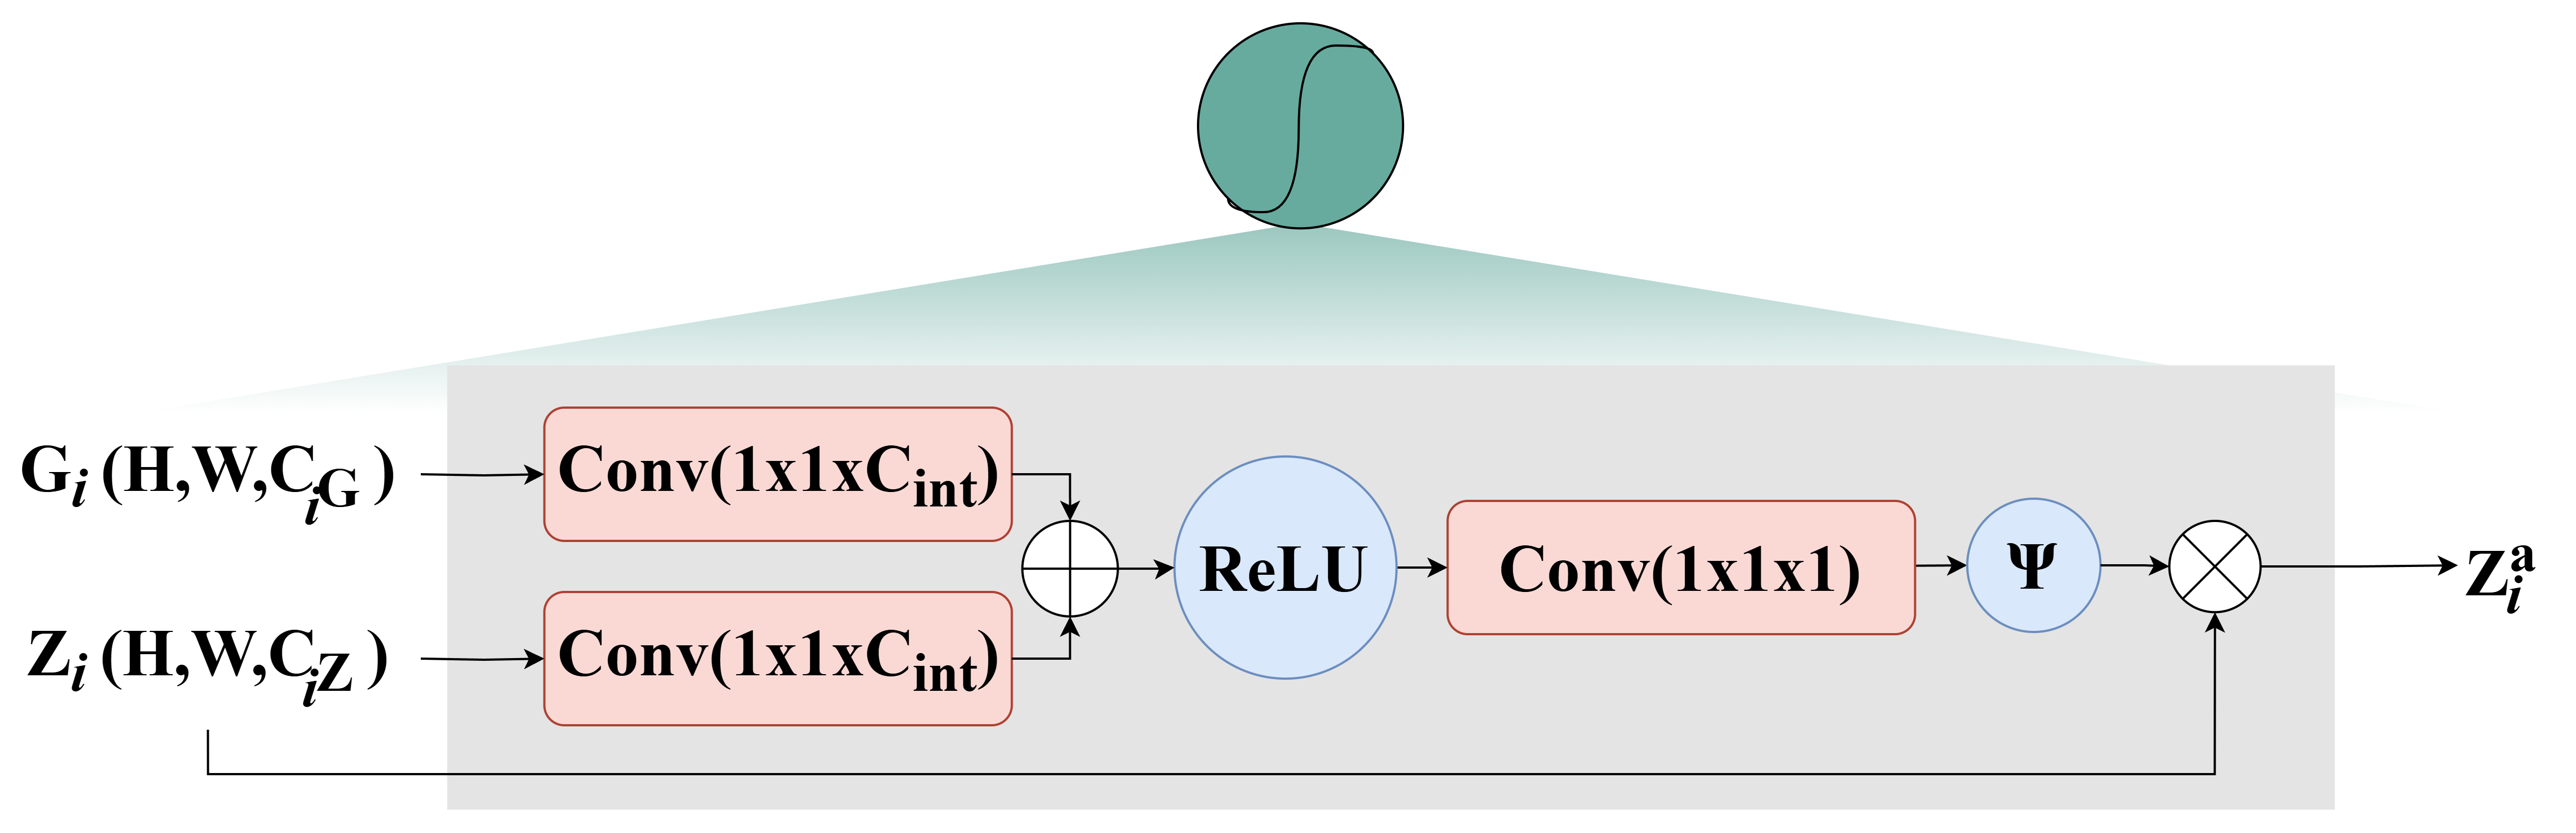

In our setup, , , , and . The channel size in the third stage reflects an experimentally optimized balance between feature richness and computational efficiency, particularly when used with corresponding multi-head attention settings , which aligns with the scale of these channels. The input image is divided into four sections, resulting in four 3D feature tensors . Each of these tensors is then processed using an cross-Attention Gate (CAG). As depicted in Figure 2, the CAG is defined by the following expression:

In this equation, the inner convolutional layers perform linear transformations using convolutional blocks, which adjust the number of channels in the input and gating signals and to intermediate feature representations with a new channel count for and , respectively. The features derived from and are combined and passed through a third convolutional layer, producing a 2D weight map. The sigmoidal activation function is then used to learn the spatial attention coefficients for each patch token. These spatial coefficients are applied to the encoder’s feature maps , representing element-wise multiplication.

For each set of extracted features from one-quarter of the input image , the gating signal is formed by concatenating the features extracted from the other three quarters, while the features from the current quarter are used as the input signal. The output features for the first quarter are determined by the following equation:

| (3) |

where is the output produced by applying the attention gate to , the tensor, where is the input signal and acts as the gating signal. In this context, for each , is defined as the concatenation of the other output tensors of the other three tensors. i.e, , , , and . The operation performs cross-attention between the tokens of the current image region and those of the other three regions. This involves calculating attention scores between tokens from different regions, allowing the model to assess the relative importance of tokens across various parts of the image.